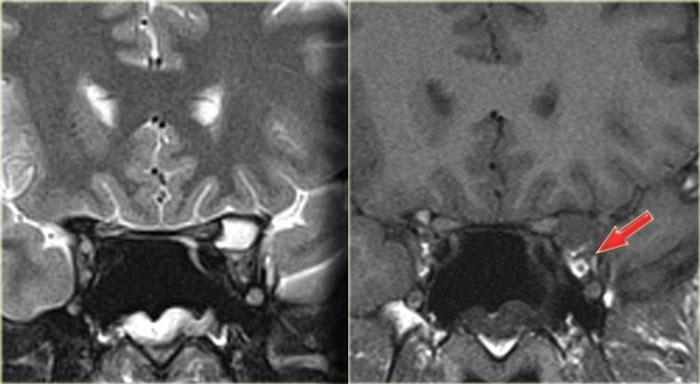

Tiếp tục xem các hình ảnh mặt phẳng coronal.

Chuỗi xung T2W mặt phẳng coronal cho thấy sự giãn rộng của mỏm yên.

Chuỗi xung T1W cho thấy mất tín hiệu mỡ bình thường so với bên phải, và lan rộng vào đỉnh hốc mắt (mũi tên đỏ).

Đây là nang nhầy của mỏm yên trước với tổn thương thứ phát dây thần kinh thị giác.